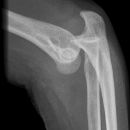

Ellenbogenluxation